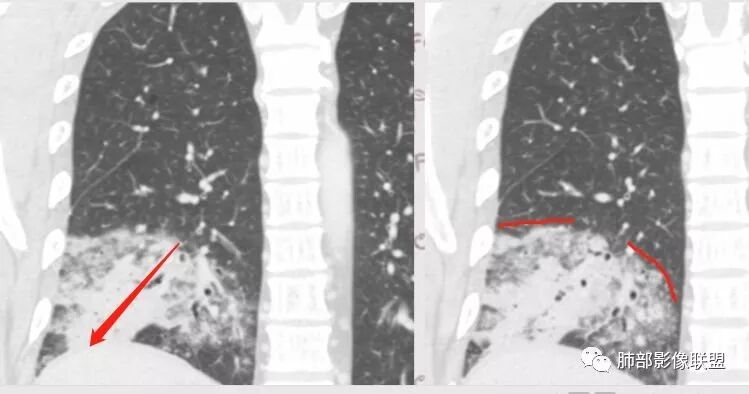

分布:沿支气管段、亚段朝外蔓延分布

实变区边缘收缩,支气管走形自然

GGO边界大部分不清楚,内有树芽征,中央间质均匀增厚

因为病灶的分布就是沿支气管走形,病灶整体就是沿段分布

吴倩南京市第一医院:第一个是分布的定位问题,南大把他分成三种,第一个肺实质肺泡来源的,第二个支气管从上面往下来的,第三个是间质来的。如图如果是肺泡本身发生的病变应该是外周大,实,往里面变小,变虚,还有支气管壁不增厚。

但是这个病例是由支气管往下,越来越淡,与支气管是平行走形,然后支气管壁增厚,还有树丫,虽然带着GGO的,分布属于支气管往下来的,这个和粘液腺癌不同,和肺炎链球菌也不同。比较符合TB,支原体这些。

病灶明显按叶、按段分布为主的,或者跟气道进来的病原菌引起气道壁的改变为主的,周围实变引起的,看CT冠状位、矢状位,如果能够沿着长轴重建更明显,就是沿着典型肺段分布的特点,如果急性沿肺段分布一般考虑气道来源。当然该患者说间质性可不可以?也可以,但是这样分布间质性也有特点。但我们周围外围分布为主,不按从肺门向外围肺叶段分布的话,那我们考虑外围的,它长轴会和胸膜平行的概念,常认为间质的。还有肺实质病变,理解是有差异的,肺隐球菌是肺实质病变?肺间质病变?应该两者都有。因为病灶在肺间质里面的,往往大片间质性病变,都是弥漫性间质病变,很少局限的。如果局限的,往往和中央间质相关的,就淋巴道局限有可能肺门淋巴结堵塞引起逆流受阻、分流受阻。或者沿着肺门淋巴结朝外围逆行性增生性增长。一般肺间质对称的,为疏松结缔组织,肺部疏松结缔组织弹性更好,纤维成分、纤维细胞多。第二巨噬细胞多。纤维化病变与免疫及相关的有关,也有特发的。间质相关性往往是弥漫的,主要其所有细胞,包括基质、细胞是相连相通的,特性是一致的,局限受累的比较少。